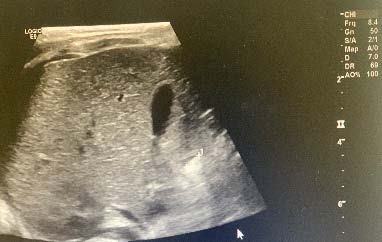

? Dedifferentiated liposarcoma ? Myxoid liposarcoma ? Pleomorphic liposarcoma ? Myxoid pleomorphic liposarcomaIn atypical lipomatous tumour/well differentiated liposarcoma adipocytic variant consists out of cells that vary substantially in size as well as cells that have Dedifferentiated liposarcoma can arise as a synchronous lesion in 90% of cases and as metachronous lesion in 10% of cases 6 . These tumours exhibit a wide morphological spectrum and histologically show areas of high grade, poorly differentiated sarcoma resembling high-grade myxofibrosarcoma, fibrosarcoma, malignant solitary fibrous tumour or pleomorphic sarcoma not otherwise specified. Dedifferentiated liposarcomas can be of variable histological grade 5 . Dedifferentiated liposarcomas is an aggressive disease, arising most commonly in the retroperitoneum and is associated with high rates of local and metastatic recurrence and disease specific mortality 7 Use of the term atypical lipomatous tumour is determined by tumour location and resectability. In locations such as the retroperitoneum, it is usually impossible to obtain a wide tumour free surgical margin of more than 2cm, thus local recurrence is common and leads to mortality, seen in the absence of dedifferentiation or metastases The introduction of computed tomography (CT), magnetic resonance imaging (MRI), and ultrasonography have greatly enhanced our capability to make the diagnosis of abdominopelvic neoplasms and determine and direct treatment, as well as observe the progress of the neoplasm and effect of treatment over time. Identification of a retroperitoneal mass at imaging is a challenging task for radiologists, however the presence of fat within a retroperitoneal lesion is helpful in refining the differential diagnosis 9 ? On ultrasound appearance it is hyperechoic and may demonstrate posterior acoustic shadowing . It is easy to recognize fat within a lesion due to its characteristic imaging appearance: